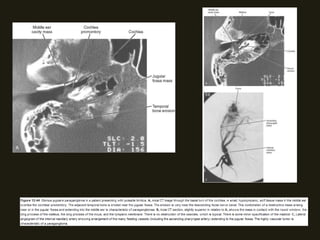

OTITE EXTERNA MALIGNA (necrozante)

TC/RM

• Espessamento dos tecidos moles do CAE; formação tecidual

• Extensão para tecidos moles adjacentes e destruição óssea

• Pode realce pelo contraste com múltiplos abscessos focais;

LESÕES INFLAMATÓRIAS OTITE EXTERNA MALIGNA (necrozante) • Infecção por Pseudomonas; • Idosos, imunodeprimidos, diabéticos; • Pode cursar com destruição óssea e acometer os tecidos moles adjacentes, inclusive a naso/orofaringe (fissuras de Santorini); • Acometimento intracraniano (meningite, osteomielite dos ossos do crânio)

TC/RM • Espessamento dostecidos moles do CAE; formação tecidual no ouvido médio e mastóide; • Extensão para tecidos moles adjacentes e destruição óssea associada; • Pode realce pelo contraste com múltiplos abscessos focais;